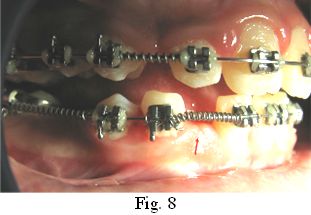

Con el objetivo de recuperar el espacio para el diente 4.2 retenido, se instala una aparatología ortodóncica que protruye el sector incisivo inferior, cerrando los diastemas anteroinferiores y centrando la línea media (Fig. 8)